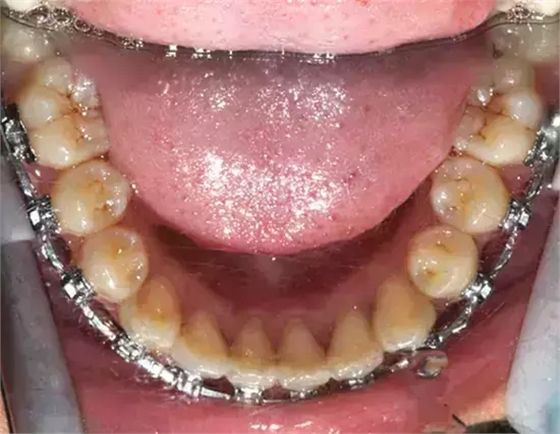

患者側(cè)面凸,鼻唇角較銳,笑時(shí)露齦笑明顯上下牙列擁擠,磨牙尖牙Ⅱ 類關(guān)系,3 度的深覆牙合,上頜中切牙伸長內(nèi)傾拔除上頜雙側(cè)的第一前磨牙,先粘上頜高轉(zhuǎn)矩的自鎖托槽排齊牙列,唇向開展上頜切牙,有一定的覆蓋,粘下頜標(biāo)準(zhǔn)轉(zhuǎn)矩托槽,上頜 1, 2 之間植入種植支抗壓入,同時(shí)后牙 5, 6 之間植入種植支抗內(nèi)收前牙,打開咬合關(guān)閉間隙。治療關(guān)鍵:前牙轉(zhuǎn)矩的控制第 1 個(gè)月 上頜粘上 Damon Q 高轉(zhuǎn)矩托槽,上 .014 熱激活 NiTi 絲。第 3 個(gè)月 上換 .014 x .025 熱激活 NiTi 絲。第 5 個(gè)月 上頜基本排齊,覆蓋增大,上換 .017 x .025 NiTi絲,下頜粘托槽,下 .014 熱激活 NiTi 絲。第 7 個(gè)月 上 .017 x .025 NiTi 絲加搖椅,下?lián)Q .014 x .025 熱激活 NiTi 絲第 9 個(gè)月 上頜換 .019 x .025 NiTi 絲加搖椅,下頜換 .017 x .025 NiTi 絲第 11 個(gè)月 下頜換 .019 x .025 加搖椅,上頜 1, 2 之間, 5, 6 之間植入種植釘,下頜出現(xiàn)散隙。第 13 個(gè)月 上頜換 .019 x .025ss 加搖椅,前牙種植釘用 Power Chain 壓低前牙(每側(cè) 100g),后牙種植釘關(guān)閉間隙(每側(cè) 150g),下?lián)Q .019 x .025ss,Power Chain 關(guān)閉間隙。第 19 個(gè)月 上頜前牙基本壓低到位去除前牙種植釘,繼續(xù)用關(guān)閉間隙,下頜散隙關(guān)閉。